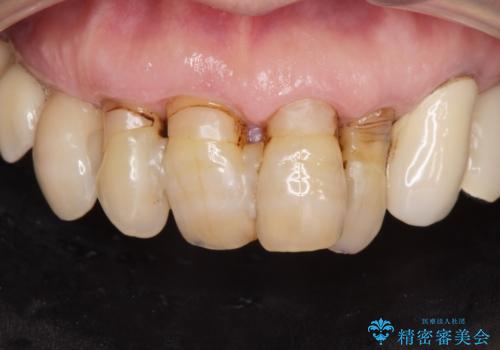

孫から口臭を指摘され来院、全顎治療で噛み合わせ、見た目、口臭全て劇的改善!